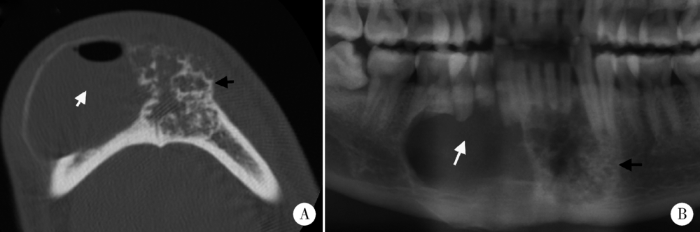

促结缔组织增生型成釉细胞瘤成骨稀疏型(Ⅲ型)

Figure 4

The sparsely ossifying type of DA (type Ⅲ)

Sparse internal ossification is observed on axial CT images (white arrow).

促结缔组织增生型成釉细胞瘤混合型

Figure 5

The hybrid type of DA

Axial CT image (A) and cropped panoramic tomography (B) shows the lesion is composed of the unicystic part (white arrows) and ossification part of DA (black arrows).